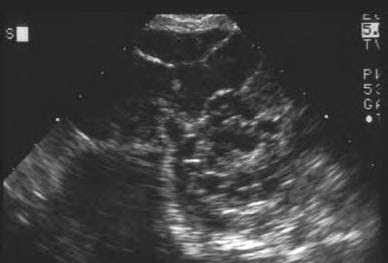

Endoscopia Ginecologica: Ecografía en cancer de ovario 😈